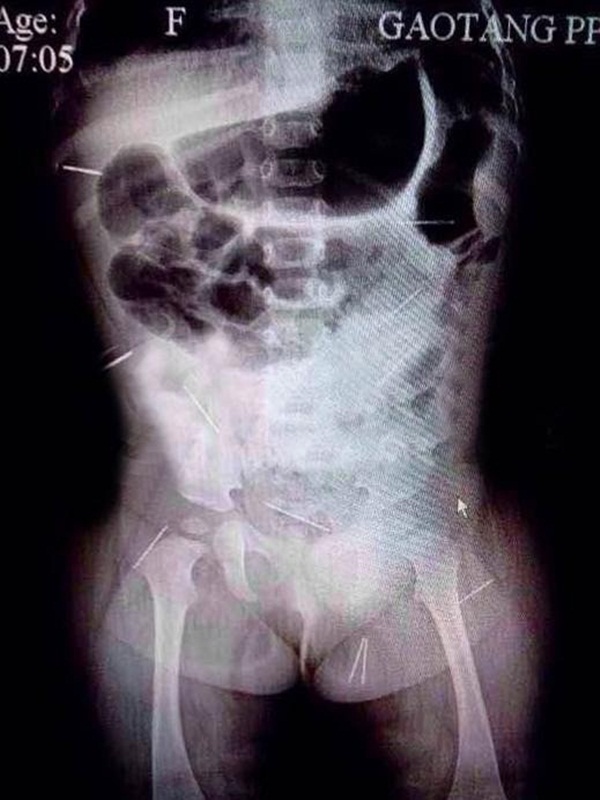

12 cây kim năm quanh cơ thể của Phạm Tử Huyên.

Nhìn vào kết quả chụp X-quang, vợ chồng cô suy sụp khi phát hiện có 12 cây kim với đủ loại hình dáng đâm vào cơ thể của Tử Huyên. Trong hình chụp có thể thấy được, những chiếc kim này được phân phối ở mông, khoang bụng, xương chậu và những bộ phận khác. Nhận thấy tình hình không còn là vấn đề sức khỏe thông thường, bố của Tử Huyên lập tức báo cảnh sát. Do điều kiện hạn chế ở bệnh viện huyện nên Tử Huyên được chuyển đến Bắc Kinh để tiến hành phẫu thuật lấy 12 cây kim ra khỏi cơ thể bé gái.

Theo phân tích của các bác sĩ, 12 cây kim được đâm vào những bộ phận nguy hiểm trên người đứa bé, trong đó có 5 cây kim nằm gần các cơ quan nội tạng. Một trong số đó nằm sát tim và có một số kim thậm chí còn bị rỉ sét. Ngày 28/10/2014, các bác sĩ ở bệnh viện Bắc Kinh tiến hành phẫu thuật để lấy 12 cây kim ra ngoài. Dưới sự hỗ trợ của siêu âm B và nội soi, bác sĩ đã cẩn thận lấy kim từ đùi, lách và thận của Tử Huyên. Đáng ngạc nhiên nhất là sau khi 12 cây kim được lấy ra, các bác sĩ phát hiện rằng chỉ có 2 cây kim được dùng trong may thêu hằng ngày, 10 cây kim còn lại là kim dùng trong y tế.